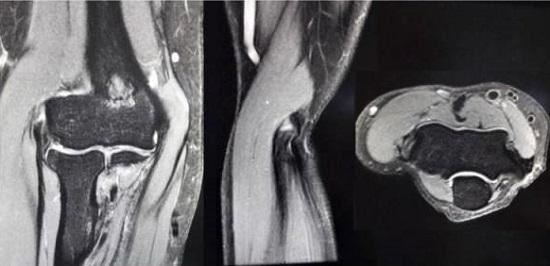

网球肘影像

1、肘部局部感染。应在局部感染得到控制后再考虑实施网球肘手术治疗。2、肘关节僵硬。肘关节僵硬者,应先设法解决肘关节僵硬问题,否则即便实施清创术,运动功能障碍也不能解除。另外,肘关节处的手术易于引发软组织粘连及异位骨化,肘关节僵硬者更要谨慎。3、之前接受过肘部手术者。应充分考虑骨骼和软组织的愈合问题。

肘关节处的异位骨化